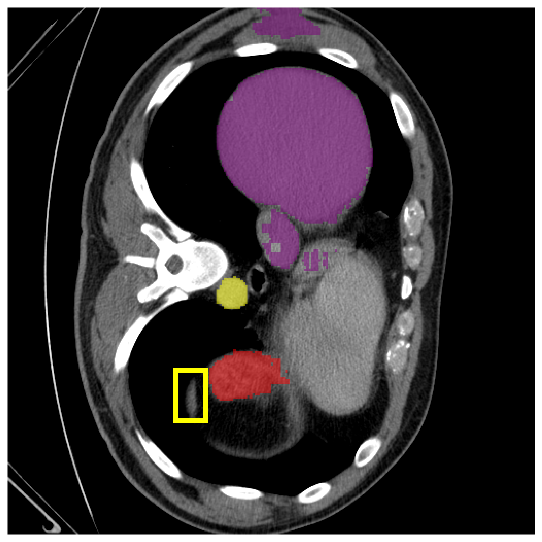

4.3.2 Visual Comparisons

Visualization of our method on the Synapse and ACDC datasets is shown in Fig. 3(a) and Fig. 3(b). For the Synapse dataset illustrated in Fig. 3(a), FCT failed to accurately segment SM and GB, while MERIT achieved precise segmentation of SM but struggled with GB. In contrast, our method achieved accurate segmentation of both SM and GB. Regarding the ACDC dataset shown in Fig. 3(b), while previous methods achieve comparable segmentation of the Myo and LV to the GT, they exhibit noticeable errors on the RV, including invasion into adjacent organs and misrecognition. On the other hand, our method accurately segments across all three structures Myo, LV, and RV, performing as precisely as the GT. We demonstrate the superiority of our method quantitatively and qualitatively.